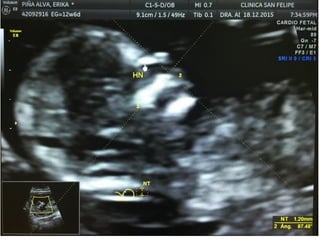

HUESO NASAL

• Corte sagital medio. Magnificación de la imagen.

• En esta posición tenemos que ver tres líneas :

– 1-2: 2 líneas paralelas más cercanas a la frente del feto,

la más externa corresponde a la piel y la más interna al

hueso nasal (de más grosor y ecogenicidad)

– 3: Otra línea a un nivel más alto que la piel que es la

punta de la nariz.

HUESO NASAL • Cortesagital medio. Magnificación de la imagen. • En esta posición tenemos que ver tres líneas : – 1-2: 2 líneas paralelas más cercanas a la frente del feto, la más externa corresponde a la piel y la más interna al hueso nasal (de más grosor y ecogenicidad) – 3: Otra línea a un nivel más alto que la piel que es la punta de la nariz.